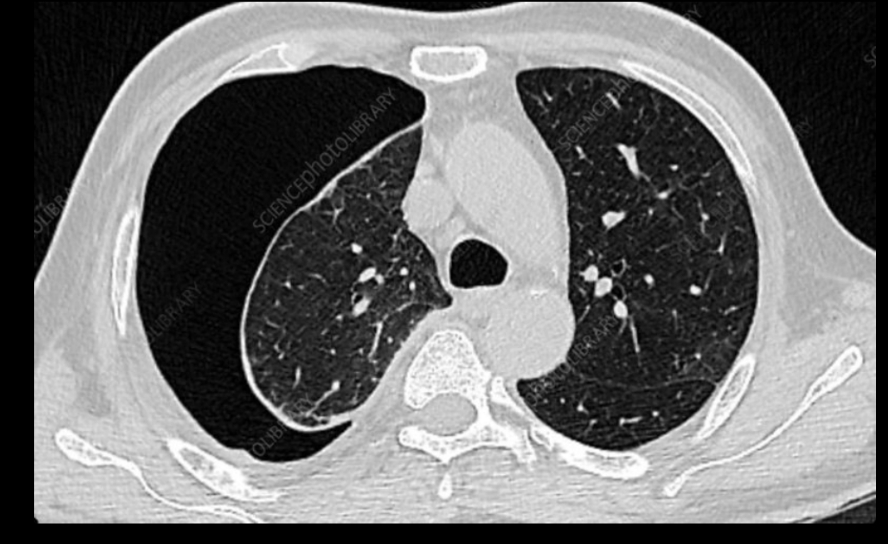

Qué se ve en un neumotórax en Rx. y TC?

• Hiperclaridad

• Pérdida de trama vascular

• pulmón colapsado